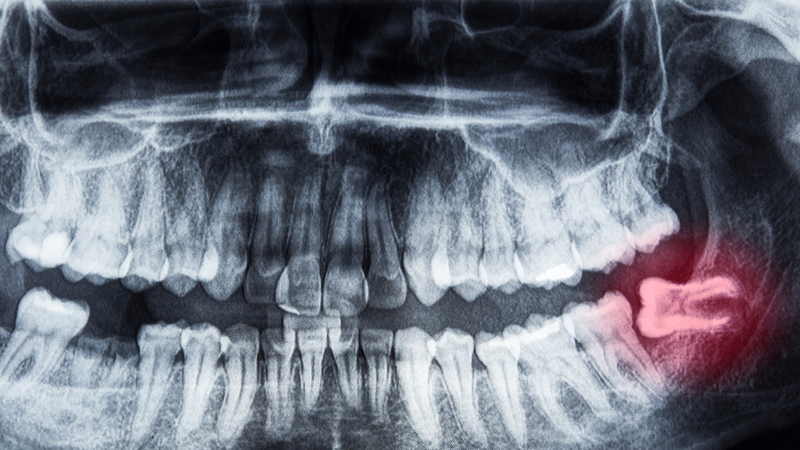

Quy trình phẫu thuật thường bắt đầu bằng việc khám và chụp X-quang để đánh giá vị trí và tình trạng của răng khôn. Trước khi tiến hành nhổ, bệnh nhân sẽ được gây tê cục bộ để giảm đau. Sau đó, nha sĩ sẽ thực hiện các bước để nhổ răng, bao gồm mở nướu, loại bỏ một phần xương hàm nếu cần thiết và nhổ răng khôn.

Ngoài ra, nếu răng khôn đang làm hỏng các răng lân cận hoặc gây ra lệch cấu trúc hàm, việc loại bỏ nó sẽ giúp duy trì sức khỏe răng miệng tổng thể. Nha sĩ sẽ thực hiện các kiểm tra lâm sàng và chụp X-quang để đánh giá tình trạng răng khôn và đưa ra quyết định phù hợp.